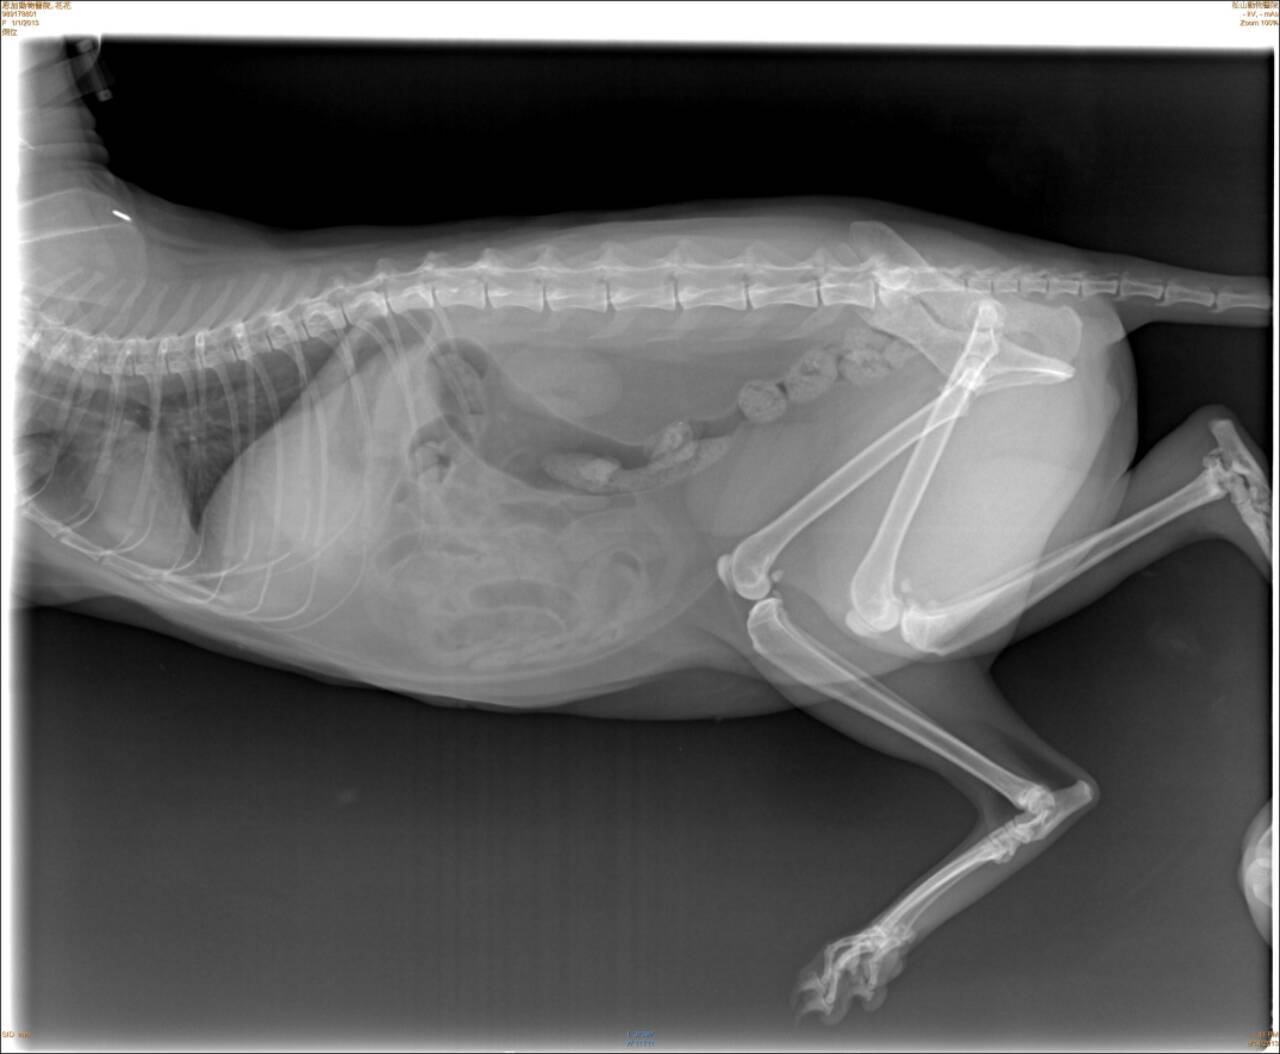

趕緊送往配合醫院~恩加動物醫院檢查。經觸診及照X光片,醫生表示花花的左後肢腳跟關節粉碎性骨折、脫水、白血球上升到三萬多。

經與醫師討論請教,醫師建議不宜動刀、因為粉碎性骨折無法接合只能打板固定,但如此一來反而會讓腳僵直無法動彈。預計先施打點滴補充體力、抗生素、止痛針,等貓咪穩定後要讓貓自行活動進行腳的復健,但已不適合回到接頭流浪了。

8/14住院,照X光片。